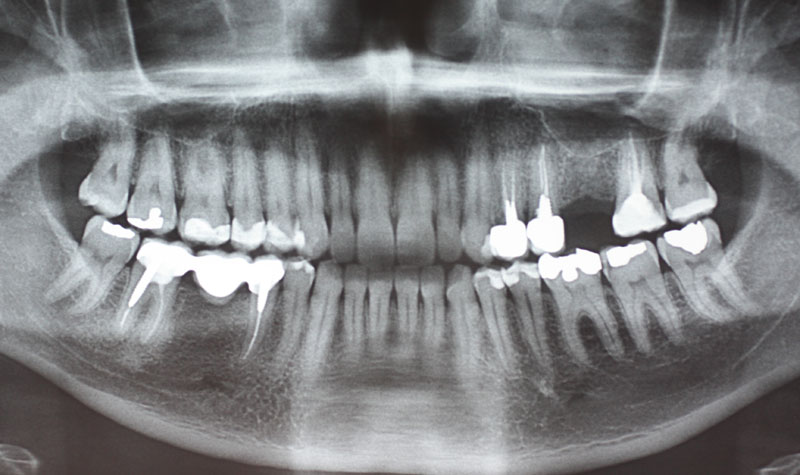

Si noti la perfetta integrazione dell'impianto a livello tissutale e la perfetta integrazione estetica del manufatto protesico.

L'uso di un impianto tissue level ha il grande vantaggio per i nostri pazienti di non dover subire un secondo rientro chirurgico. L'utilizzo è limitato ai casi da noi selezionati.